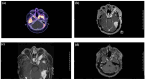

Meningiomas are the most common primary intracranial tumors, with TRAF7 mutations identified in ~25% of cases. These mutations, associated with NFκB pathway activation, are linked to higher recurrence rates than other low-grade-associated mutations. We report a 49-year-old Caucasian woman with recurrent TRAF7-mutated World Health Organization Grade 2 meningiomas. Initially diagnosed with World Health Organization Grade 1 meningiomas in 2015, her disease progressed to Grade 2 chordoid meningioma by 2021. Molecular profiling revealed a TRAF7 exon 20 (p.R653Q) mutation and PMS2 deletion. Multiple surgical resections, radiation, and systemic therapies, including lanreotide, bevacizumab, and pembrolizumab, were employed, with pembrolizumab showing a favorable response due to mismatch repair deficiency. This case highlights the molecular and histological evolution of TRAF7-mutated meningiomas and the potential of immunotherapy in recurrent cases. The absence of targeted therapies for TRAF7-positive tumors underscores the need for mutation-specific clinical trials.